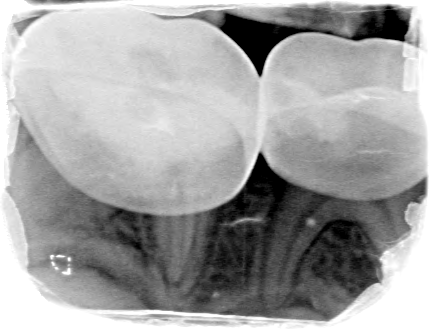

Afbeelding 3a: Röntgenfoto's op de leeftijd van 6 jaar, juli 2018.

Afbeelding 3b: Röntgenfoto's op de leeftijd van 6 jaar, juli 2018.

Afbeelding 3c: Röntgenfoto's op de leeftijd van 6 jaar, juli 2018.

Afbeelding 3d: Röntgenfoto's op de leeftijd van 6 jaar, juli 2018.

Jenny is 6 jaar. Er worden röntgenopnames en kleurenfoto’s gemaakt (Afb. 3 en 4). Op de röntgenfoto’s lijken de bovenmolaren ernstig aangetast, maar ze zijn hard en inactief. De niet-gerestaureerde bovenmolaren en kronen met gerestaureerde ondermolaren zijn vrij van ontsteking. Jenny kwam voor mondonderzoek om de 4-6 mnd.

Voor het maken van röntgenfoto’s werd een doormidden geknipt maat 0 fosforplaatje gebruikt. Maat 0 is voor veel jonge kinderen te groot en moeilijk te accepteren.